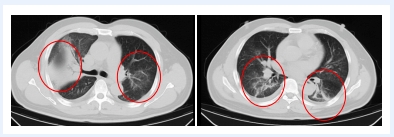

發(fā)熱門診醫(yī)生詳細詢問顧先生的既往病史,并為其進行細致的體格檢查。胸部CT結(jié)果顯示,顧先生的雙肺存在大面積的炎癥病變。

在感染科醫(yī)護團隊的精心治療與細致護理下,顧先生的發(fā)熱、咳嗽、胸悶等癥狀逐漸緩解。復(fù)查的CT結(jié)果顯示,肺部炎癥情況得到了明顯的改善。目前,顧先生已經(jīng)順利康復(fù)出院。